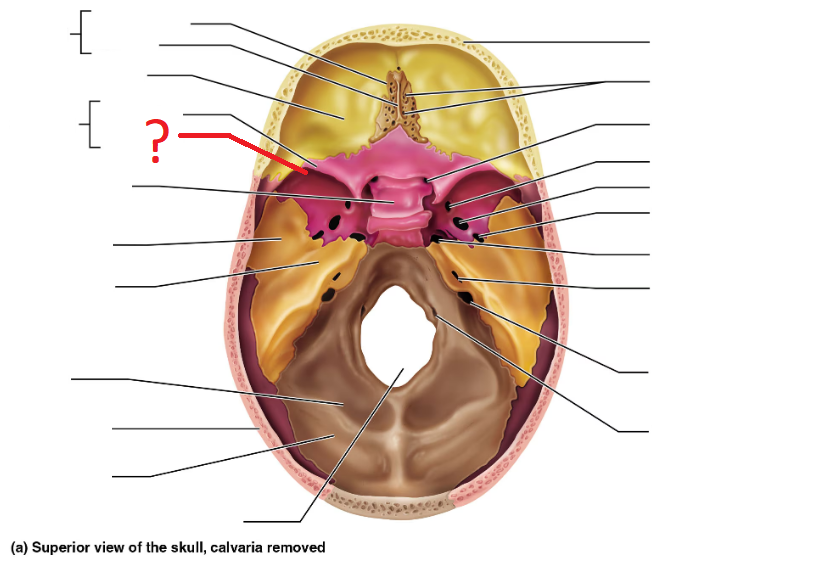

Ethmoid bone

Crista galli

Cribriform plate

Greater sphenoid wing

Lesser sphenoid wing

Sella turcica, protects pituitary gland

Foramen magnum (superior interior view)

Jugular foramen

Carotid Canal